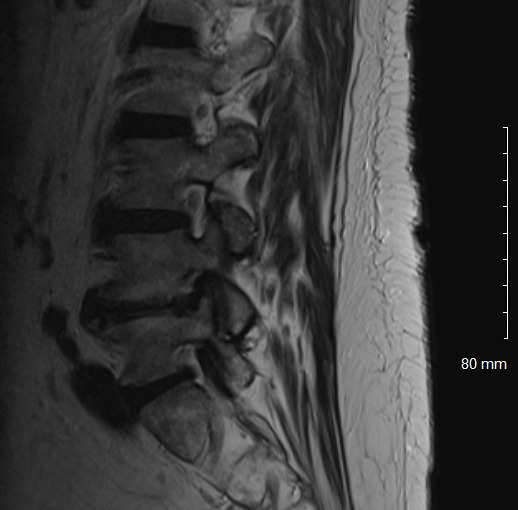

Physical examination revealed hypertonicity and tenderness in the lumbar paraspinal muscles and the left posterior hip region. He reported a pain level of 8/10 on the NPRS, reflecting both LBP and radicular symptoms. Additionally, a score of 32 out of 40 on the DVPRS indicated substantial pain-related functional impairment. A 2024 lumbar spine MRI demonstrated degenerative disc disease, arthropathy, severe left subarticular recess stenosis at L4-L5 with L5 nerve impingement, and a small left central disc extrusion at L5-S1 abutting the S1 nerve root (Figs. 1–4).

This case report documents an unexpected improvement in PLP during chiropractic treatment for LBP and radicular symptoms in a patient with a below-knee amputation. The temporary abolition of PLP reported at Visit 5, which was sustained for 2 weeks, suggests that automated lumbar long-axis distraction and myofascial release may influence the neuropathic pain pathways in amputee patients. Furthermore, lumbar distraction may reduce mechanical compression on the L5 nerve root, as seen on MRI (Figs. 1-4), potentially decreasing spinal cord hyperexcitability associated with PLP.15 Myofascial release, by addressing trigger points and muscle tension, may alter afferent input to the spinal cord, influencing pain processing.16 Chiropractic manipulation has been shown to modulate pain perception and widespread pressure sensitivity, likely through activation of descending inhibitory pathways. While these mechanisms may play a role in conditions involving central sensitization, their relevance to neuropathic pain such as PLP needs further investigation.17